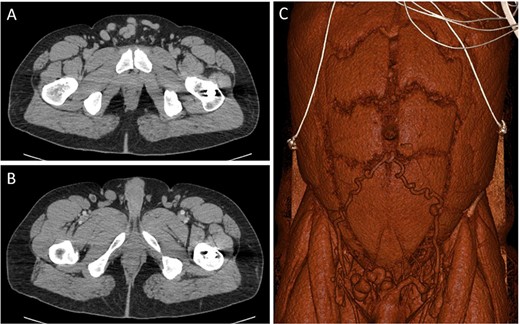

An abdominal computed tomography (CT) in the ER indicated the mass was not a hernia but instead a cluster of abdominal varicosities (Fig. 1A and B), and the patient was referred to gastroenterology for evaluation. Other past medical history was significant for a motor vehicle accident (MVA) in 2019 in which the patient sustained left femoral and right tibia-fibula fractures requiring surgery. At that time the patient was not diagnosed with DVT; however, the patient reported significant edema in his left lower extremity since the MVA and swelling in his suprapubic region. Between the patient’s ER visit 6 months prior and his presentation on at the gastroenterology clinic, the patient consulted general surgery in which the physician expressed concern of the abdominal wall varicosities being a complication of his chronic DVT. In addition, the patient reported abdominal pain in his right upper quadrant (RUQ) consistent since his MVA in 2019; however, physicians believed this to be unrelated to his DVT.

CT images through the pelvis show the dilated collateral veins (A) in the suprapubic region, initially thought to be a hernia. Solid white arrows (B) show the external pudendal vein confluences with the great saphenous veins. 3D reconstructed image (C) shows the dilated inferior epigastric and external pudendal veins, providing collateral flow around the stenosed left iliofemoral venous system.